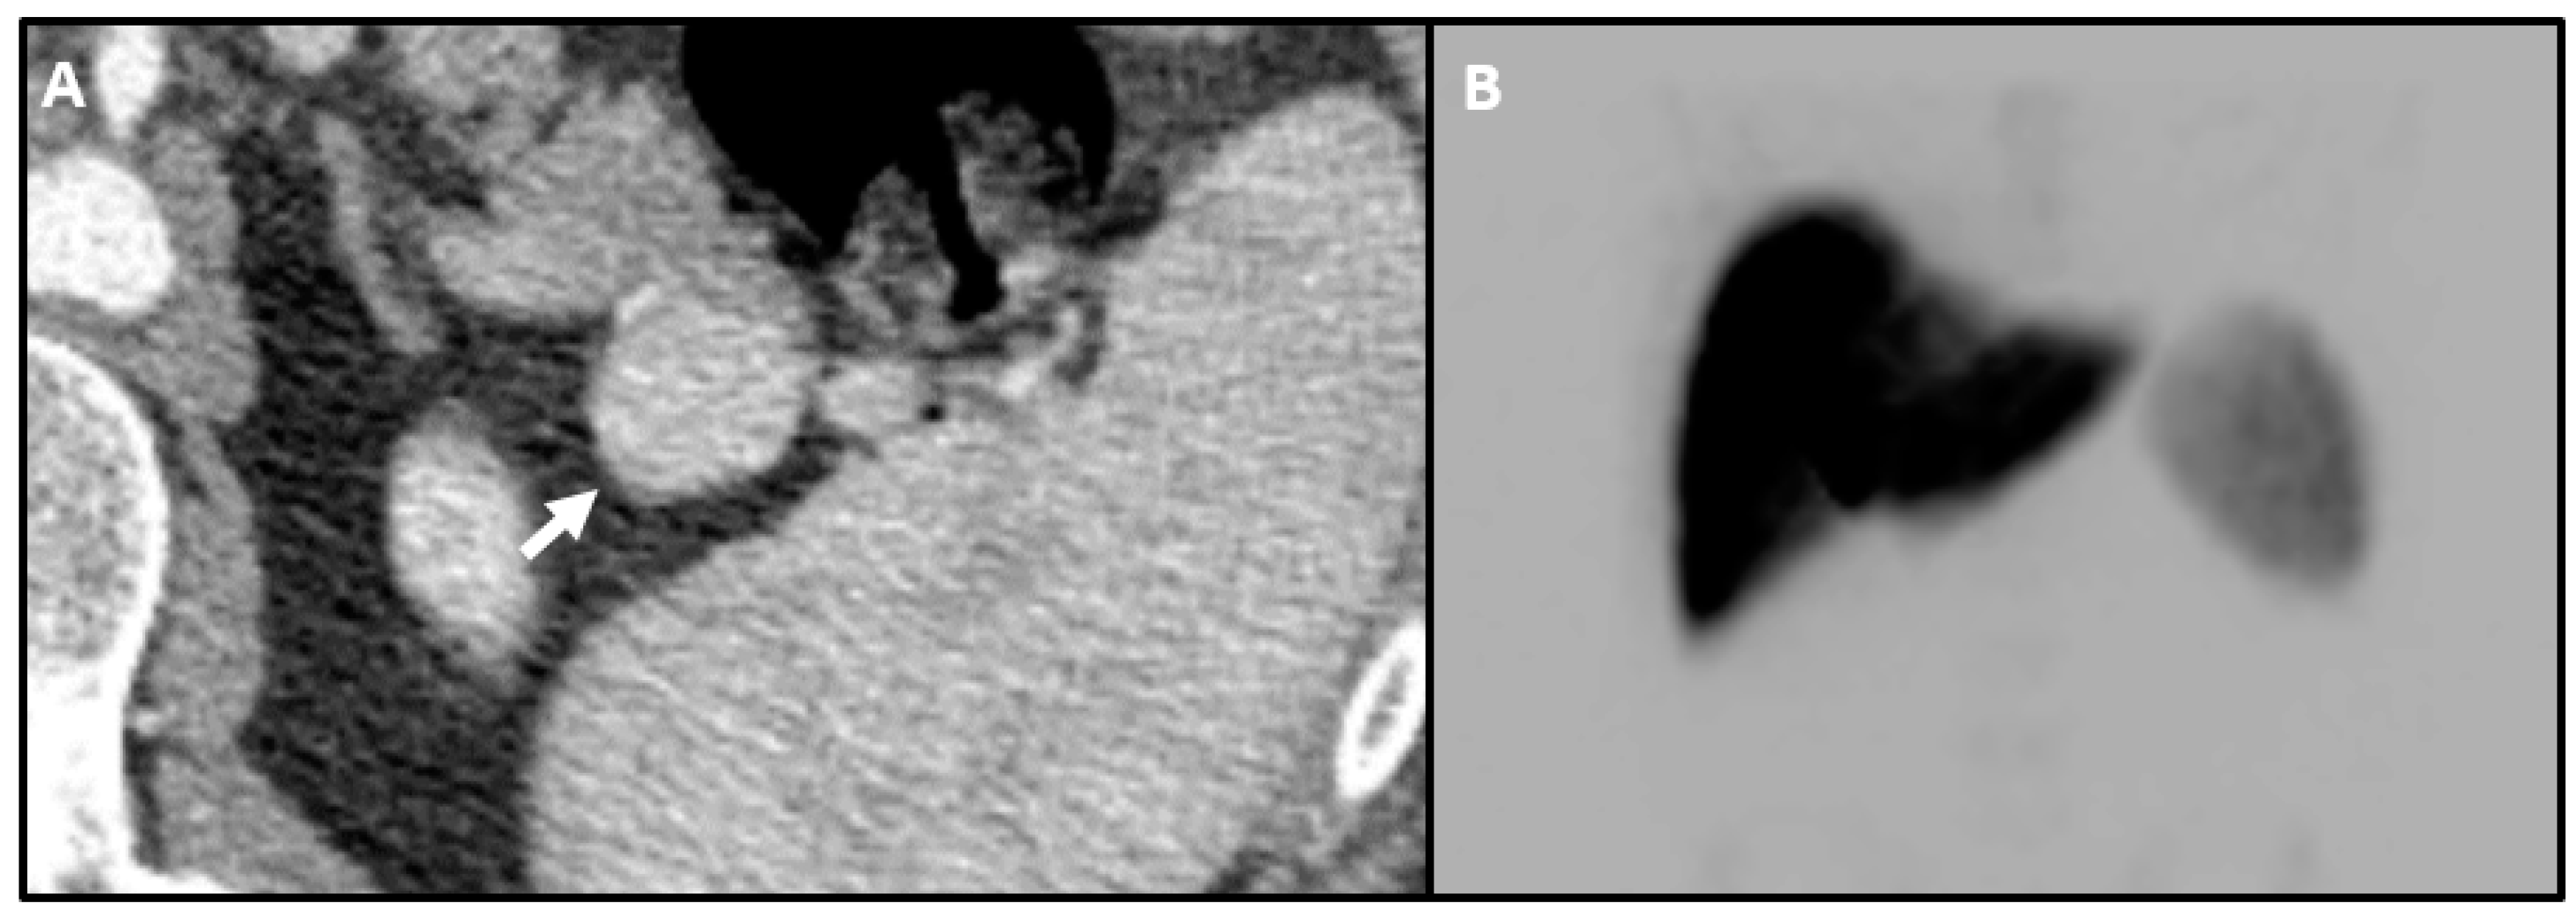

- Hayward, I.; Mindelzun, R.E.; Jeffrey, R.B. Intrapancreatic accessory spleen mimicking pancreatic mass on CT. J. Comput. Assist. Tomogr. 1992, 16, 984–985. [Google Scholar] [CrossRef]

- Uchiyama, S.; Chijiiwa, K.; Hiyoshi, M.; Ohuchida, J.; Imamura, N.; Nagano, M.; Hidaka, H.; Yorita, K.; Akiyama, Y.; Nishiura, M. Intrapancreatic accessory spleen mimicking endocrine tumor of the pancreas: Case report and review of the literature. J. Gastrointest. Surg. 2008, 12, 1471–1473. [Google Scholar] [CrossRef]

- Hwang, H.S.; Lee, S.S.; Kim, S.C.; Seo, D.W.; Kim, J. Intrapancreatic accessory spleen: Clinicopathologic analysis of 12 cases. Pancreas 2011, 40, 956–965. [Google Scholar] [CrossRef]

- Sahani, D.V.; Bonaffini, P.A.; Fernandez-Del Castillo, C.; Blake, M.A. Gastroenteropancreatic neuroendocrine tumors: Role of imaging in diagnosis and management. Radiology 2013, 266, 38–61. [Google Scholar] [CrossRef]

- Shah, M.; McClelland, A.; Moadel, R.; Javed, A.A.; Freeman, L.M. Splenule disguised as pancreatic mass: Elucidated with SPECT liver-spleen scintigraphy. Clin. Nucl. Med. 2014, 39, 405–406. [Google Scholar] [CrossRef]